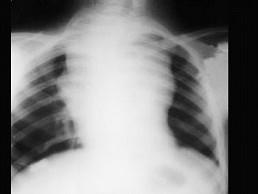

问题 血友病患者突发胸闷,气急,体查见颈静脉显露,嘴唇发干,影像学检查如图,最可能的诊断为 ( )

选项 A、纵隔积液 B、胸腺瘤 C、淋巴瘤 D、结节病 E、纵隔自发性出血

答案 E